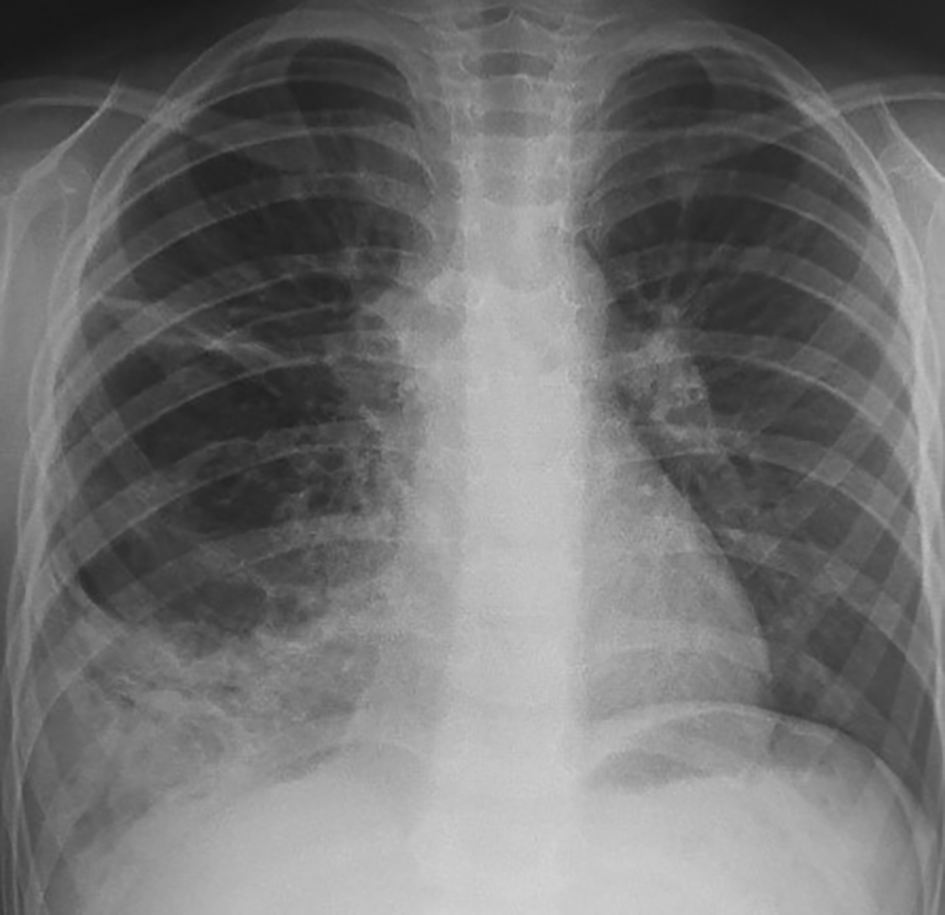

A five-year-old child was referred to our department in September 2023 because an abnormal pulmonary density of the lower right hemithorax. His past medical history revealed recurrent admissions for right pneumonia during the last two years. The patient complained of chronic productive cough without chest pain or hemoptysis. Physical examination did not reveal abnormalities apart from a decrease in breath sounds in the right lung. Chest radiography revealed a heterogeneous right opacity above the diaphragm as showed in Figure 1.